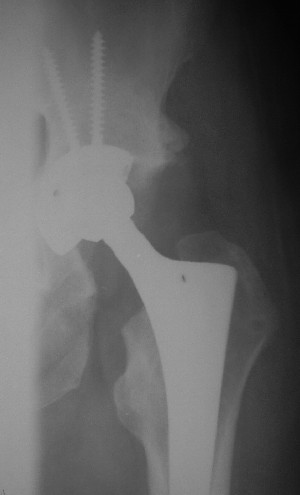

После протезирования прямой 5/04/04

Больной 18 мая 2003 года в автоаварии получил перелом левой вертлужной впадины, вывих бедра. Госпитализирован в один из стационаров области.Вывих вправлен. В последствии бедро вывихивалось еще дважды. На консультацию был представлен снимок от 19.05.03г., больной переведен к нам 3.06.03г. Снимок при поступлении - перелом впадины, задне-верхний вывих бедра. 05.06.2003 г. выполнено открытое вправление вывиха левого бедра и остеосинтез стенки вертлужной впадины двумя винтами. Послеоперационный период без осложнений. Объем движений в левом тазобедренном суставе восстановился полностью. Выписан на амбулаторное лечение в удовлетворительном состоянии с рекомендациями 3 месяца ходить на костылях без нагрузки на оперированную конечность. На контрольных рентгенограммах левого тазобедренного сустава 13.10.2003 г. - признаки консолидации перелома; плотность, форма головки и состояние суставных поверхностей удовлетворительные. Разрешена дозированная осевая нагрузка, на конечность с использованием дополнительной опоры. 19.12.2003 г. больной обратился с жалобами на боли в левом тазобедренном суставе. На рентгенограммах левого тазобедренного сустава 19.12.2003 г., 20.02.04г. - асептичекий некроз головки бедра. 5.04.04г. - эндопротез. Сейчас ходит без трости, не хромает. Особенность эндопротезирования - при удалении винтов прослежена линия перелома заднего края впадины и предложено установить чашку несколько меньшего диаметра, чтобы она была покрыта несломанной частью.